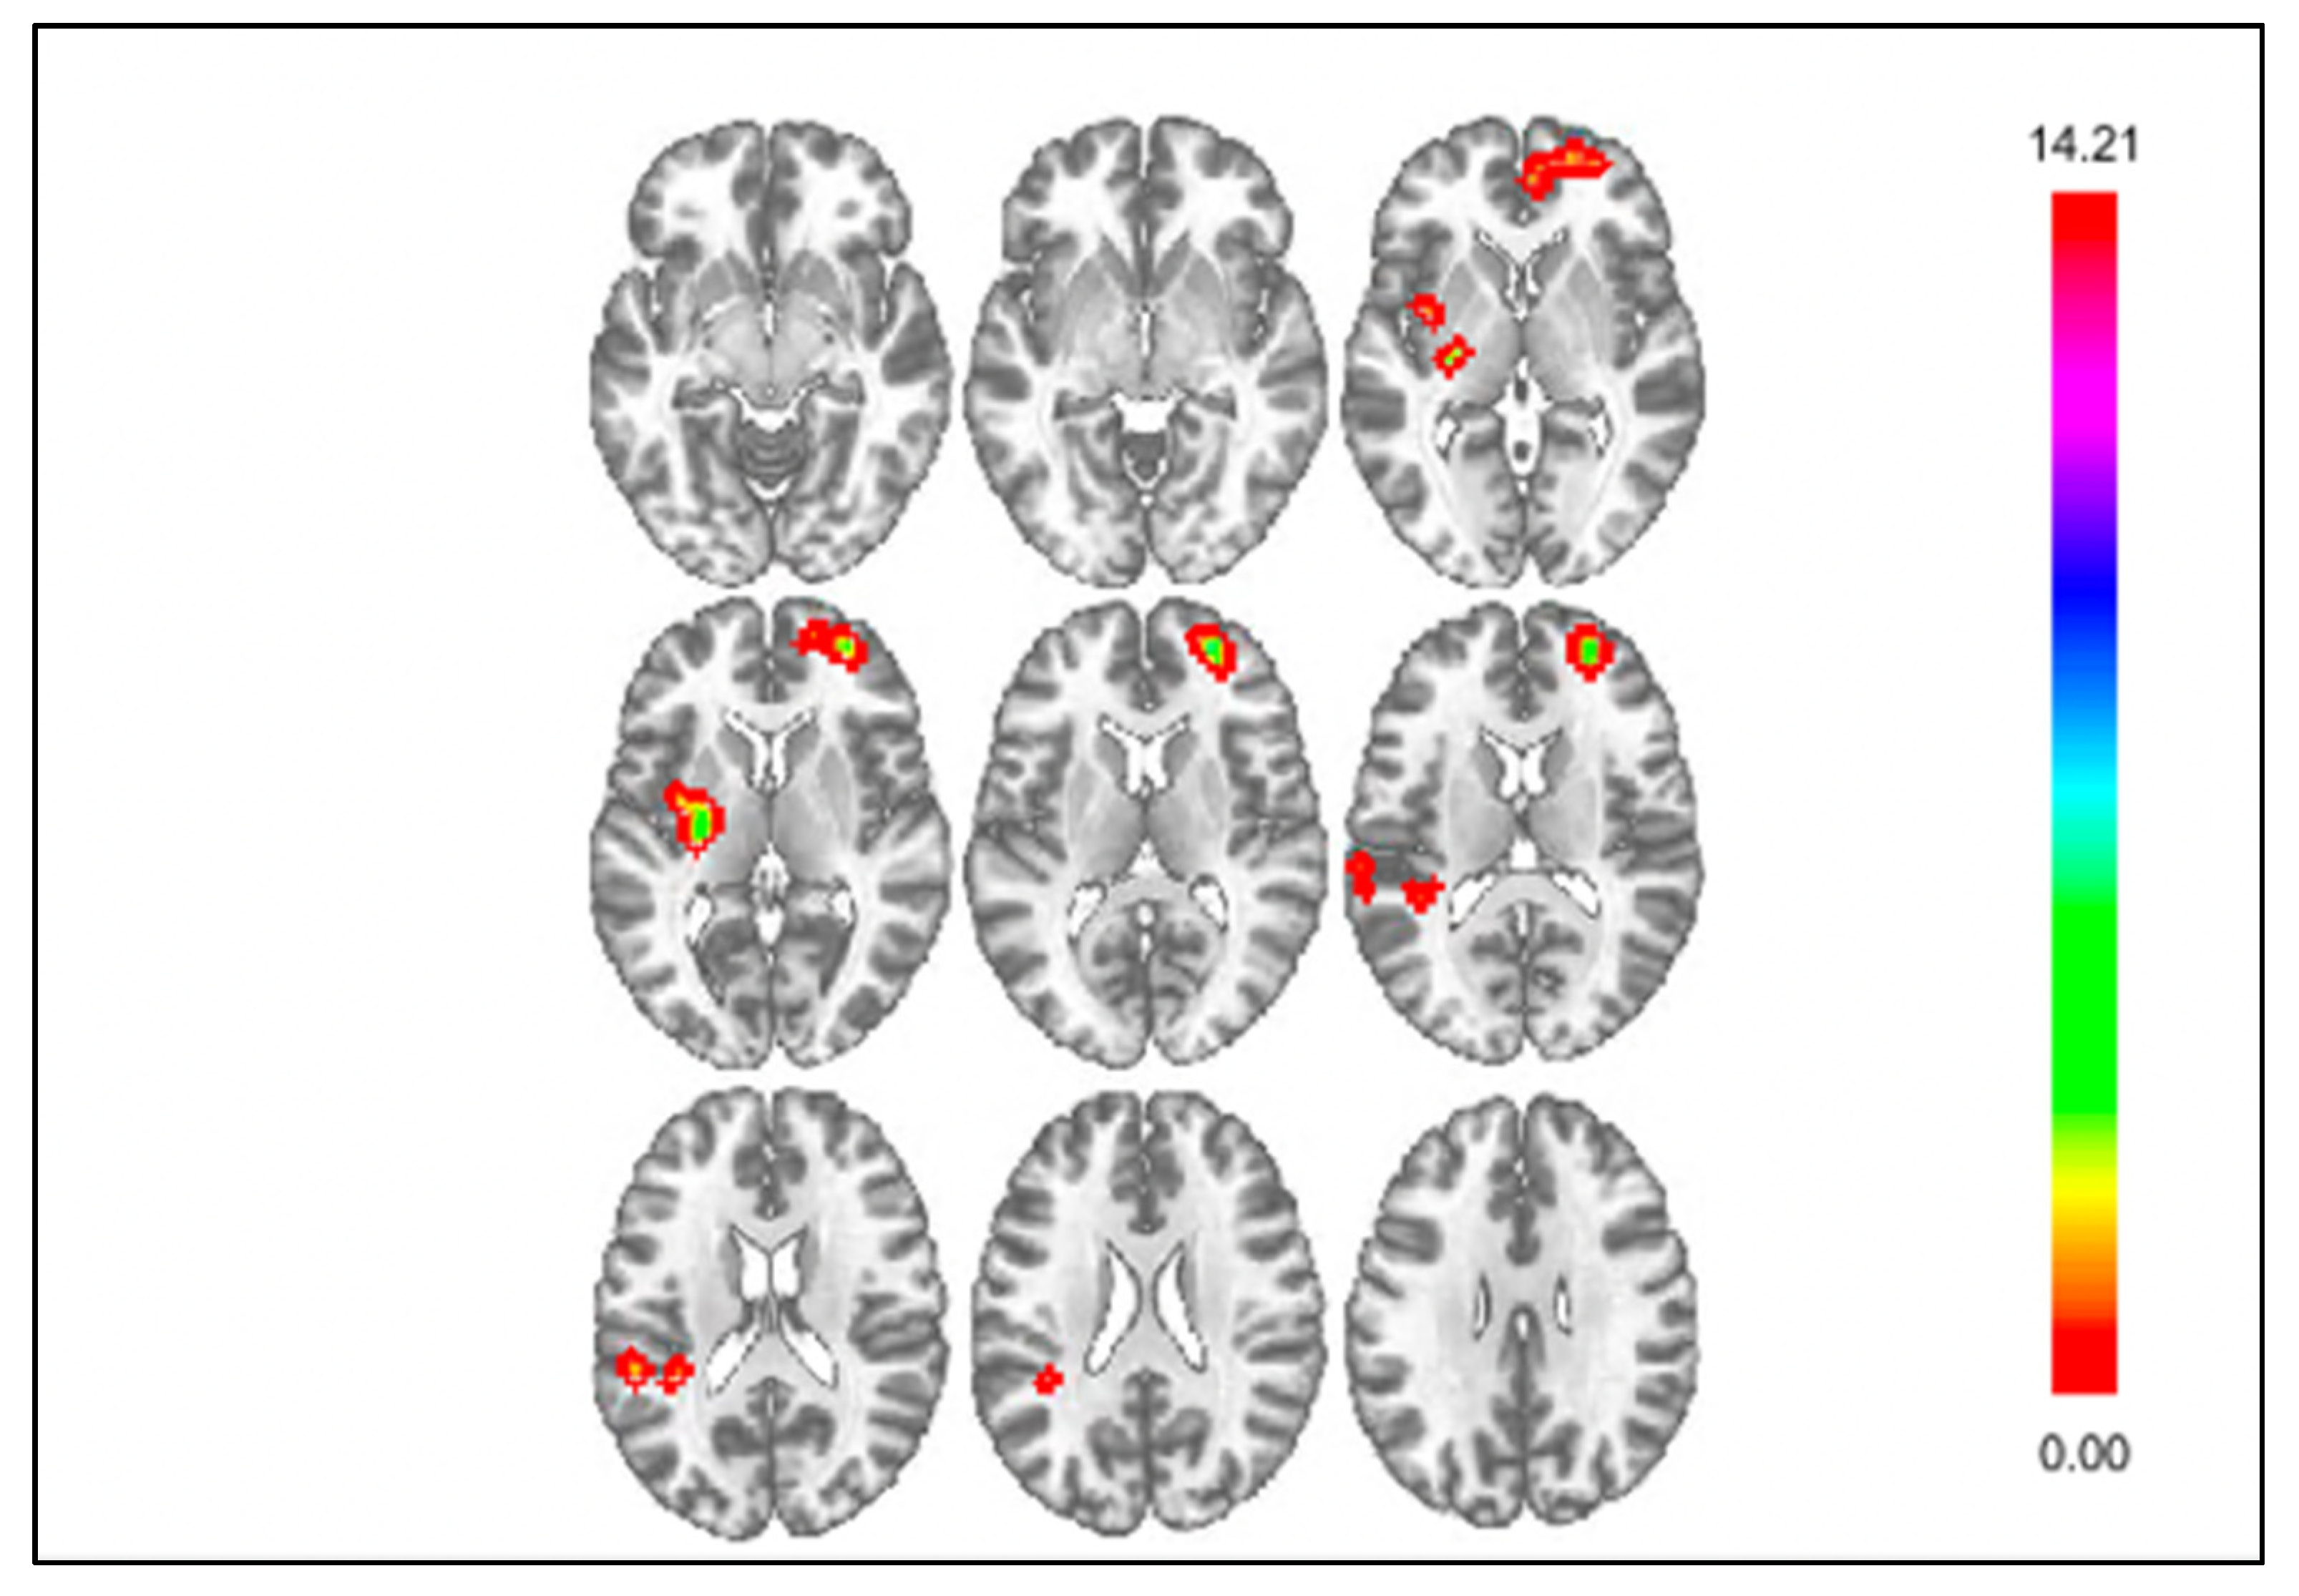

3.2. Results of Exploratory Connectivity Analyses

| Seed | Cluster Location | Cluster Size | Coordinates | Statistic | ||

| kE | x | y | z | Z | ||

| Monetary Loss | ||||||

| DS Seed | vmPFC | 112 | +24 | +57 | +12 | 4.47 |

| Insula | 61 | −27 | −12 | +06 | 4.29 | |

| Parietal Operculum Cortex | 55 | −39 | −39 | +18 | 3.90 | |

| mPFC Seed | n.s. | --- | --- | --- | --- | --- |

| Insula Seed | Supramarginal Gyrus | 41 | −60 | −33 | +42 | 4.00 |

| Social Rejection | ||||||

| DS Seed | Cerebellum | 77 | +06 | −84 | −42 | 4.34 |

| mPFC Seed | Central Opercular Cortex | 102 | −57 | −21 | +15 | 5.12 |

| Insula Seed | n.s. | --- | --- | --- | --- | --- |

| Monetary Gain | ||||||

| DS Seed | Parietal Operculum Cortex | 51 | +51 | −21 | +24 | 4.5 |

| Insula Seed | vmPFC | 52 | −24 | +69 | −06 | 3.92 |

| Social Acceptance | ||||||

| DS Seed | n.s. | --- | --- | --- | --- | --- |

| mPFC Seed | Parietal Operculum Cortex | 283 | −51 | −36 | +15 | 4.63 |

| Insula Seed | DS | 53 | −03 | +03 | +06 | 4.88 |